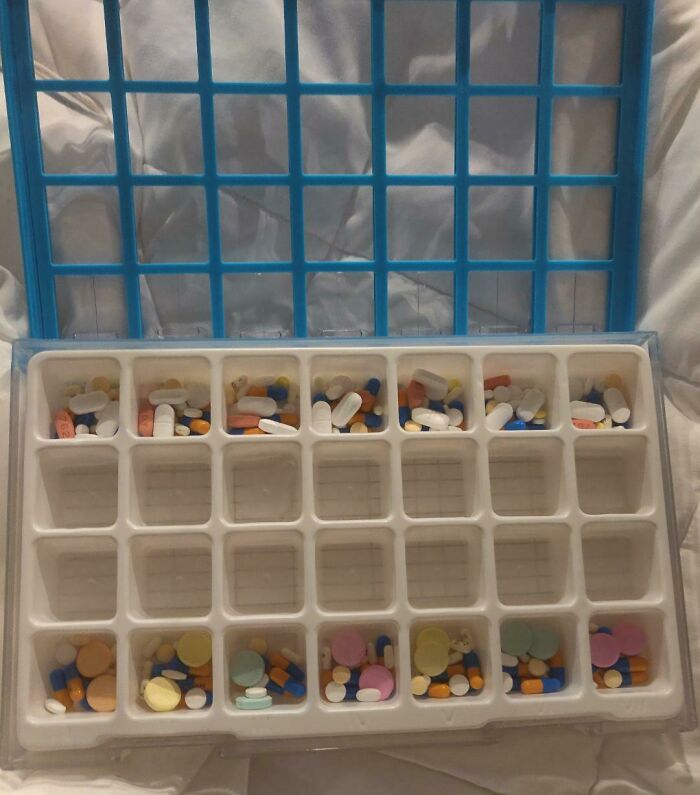

#37 The Amount Of Medication I Have To Take In A Week After A Kidney Transplant

Image credits: bjamesk4